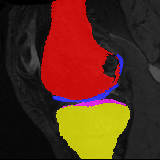

Moving Target Mono-0 Mono-5 DA-1 DA-5 Mono-200 Refer to caption Refer to caption Refer to caption Refer to caption Refer to caption Refer to caption Refer to caption Refer to caption Refer to caption Refer to caption Refer to caption Refer to caption Refer to caption Refer to caption

Figure 2:  Examples of knee MRI registration (top) and brain MRI segmentation (bottom) results. Top: The first two columns are the moving image/segmentation and the target image/segmentation followed by the warped moving images (with deformation grids)/segmentations by different models. Bottom left to right: original image, manual segmentation, and predictions of various models. Mono-i𝑖i and DA-i𝑖i represent the mono- and DA models with i𝑖i manual segmentations respectively.

Results: All trained networks are evaluated using Dice overlap scores between predictions and the manual segmentations for the segmentation network, or between the warped moving segmentations and the target segmentations for the registration network. Tabs. 1 and 2 show results for the knee and brain MRI experiments respectively in Dice scores (%). Fig. 2 shows examples of knee MRI registrations and brain MRI segmentations.

Knee results: On knee MRIs, our method improves segmentation scores over separately learned networks by about 1.2 and 0.5, and registration scores increase by about 3.1 and 3.0, when training with 5 and 10 manual segmentation respectively. Especially for the challenging cartilage structures, our joint learning boosts segmentation by 1.4 and 0.7, and registration by 5.5 and 5.2 for N=5 and N=10 respectively.

Qualitative results: DA achieves more anatomically consistent registrations than the mono-networks on the knee (Fig. 2) and Brain MRI samples (see supplementary material).

Moving Target Mono-0 Mono-21 DA-1 DA-21 Mono-65 Refer to caption Refer to caption Refer to caption Refer to caption Refer to caption Refer to caption Refer to caption Refer to caption Refer to caption Refer to caption Refer to caption Refer to caption Refer to caption Refer to caption

Figure 4: Examples of brain MRI registration (top) and knee MRI segmentation (bottom) results. Top: The first two columns are the moving image/segmentation and the target image/segmentation followed by the warped moving images/segmentations by different models. Bottom left to right: original image, manual segmentation, and predictions of various models. Mono-i𝑖i and DA-i𝑖i represent the mono- and DA models trained with i𝑖i manual segmentations respectively.